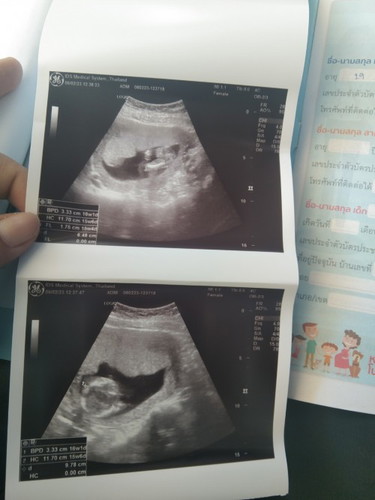

อันตราซาว 2 ครั้ง อายุครรภ์ไม่ตรงสองครั้งเลยคะ คนละหมอนะคะ ครั้งแรกบอก กำหนดคลอด 31 กค 66 วันนี้มาซาวครั้ง 2 หมอบอก 25 กค 66 คะช่วยแม่ๆดูหน่อยนะคะ สองภาพสองครั้งคะ

อายุครรภ์ในซาว วัดจากขนาดของเด็กค่ะ ว่าขนาดนี้อายุครรภ์ประมานไหนค่ะ